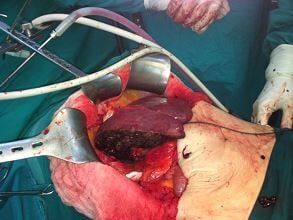

Οι εικόνες είναι από προσωπικά χειρουργεία και οι ασθενείς έχουν χορηγήσει τη συγκατάθεση τους.

Η Ηπατεκτομή αποτελεί μία επέμβαση υψηλού κινδύνου η οποία διενεργείτε από εξειδικευμένους και έμπειρους χειρουργούς ήπατος. Ο ρόλος της χειρουργικής ήπατος στην αντιμετώπιση του καρκίνου έχει αλλάξει σημαντικά τα τελευταία χρόνια με σημαντική μείωση της θνητότητας, της νοσηρότητας που συνοδεύετε από αύξηση της μακροχρόνιας επιβίωσης. Η καλύτερη κατανόηση της ανατομίας του ήπατος, η βελτιωμένη περί-εγχειρητική φροντίδα, η εξέλιξη των αναισθησιολογικών τεχνικών, η εξέλιξη στην απεικόνιση και η χρήση νέων τεχνολογιών έχει ως αποτέλεσμα τη βελτίωση των άμεσων αλλά και απώτερων αποτελεσμάτων. Επιπλέον ή βελτίωση των χειρουργικών τεχνικών είχε ως αποτέλεσμα τη δυνατότητα εκτομής όγκων του ήπατος που στο παρελθόν θεωρούνταν ανεγχείρητα.

Ηπατεκτομή ορίζεται η χειρουργική αφαίρεση όλου ή μέρους του ήπατος. Η πλήρης αφαίρεση του ήπατος γίνεται στην περίπτωση μεταμόσχευσης ήπατος, όπου αφαιρείτε το πάσχον ήπαρ και αντικαθιστάτε με το υγειές. Πιο συχνή η μερική ηπατεκτομή στην οποία αφαιρείτε ένα μέρος του ήπατος. Μερική Ηπατεκτομή γίνετε για την αντιμετώπιση καλοηθών και κακοήθων βλαβών του ήπατος.